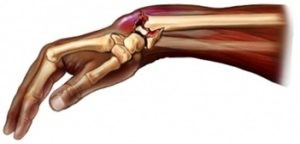

У травматологов есть такое понятие, как «перелом луча в типичном месте». Это связано с тем, что подавляющее большинство случаев перелома (почти 75%) приходится на дистальную часть кости (расположенную ближе к кисти руки).

Перелом средней и проксимальной (расположенной ближе к локтю) части лучевой кости встречается всего лишь в 5 % случаев.